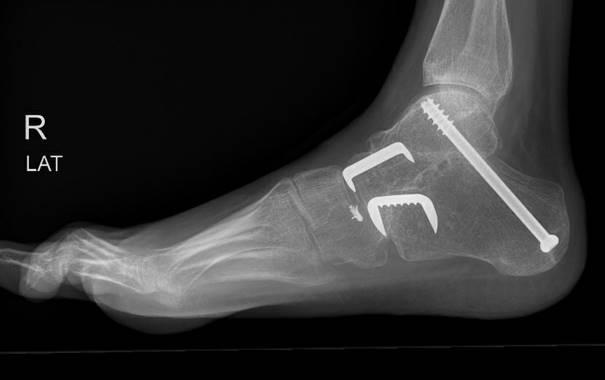

Er worden meestal drie incisies gemaakt: één aan de buitenkant, één aan de binnenkant van de voet en één onder de hiel. Hierna wordt het kraakbeen van het onderste sprong- en middenvoetsgewricht geheel verwijderd. De botten worden met meerdere schroeven en eventueel één of meerdere krammen in de juiste positie vastgezet. De huid wordt meestal gesloten met hechtingen die vanzelf oplossen.

Voorbeeld van een röntgenfoto na de operatie